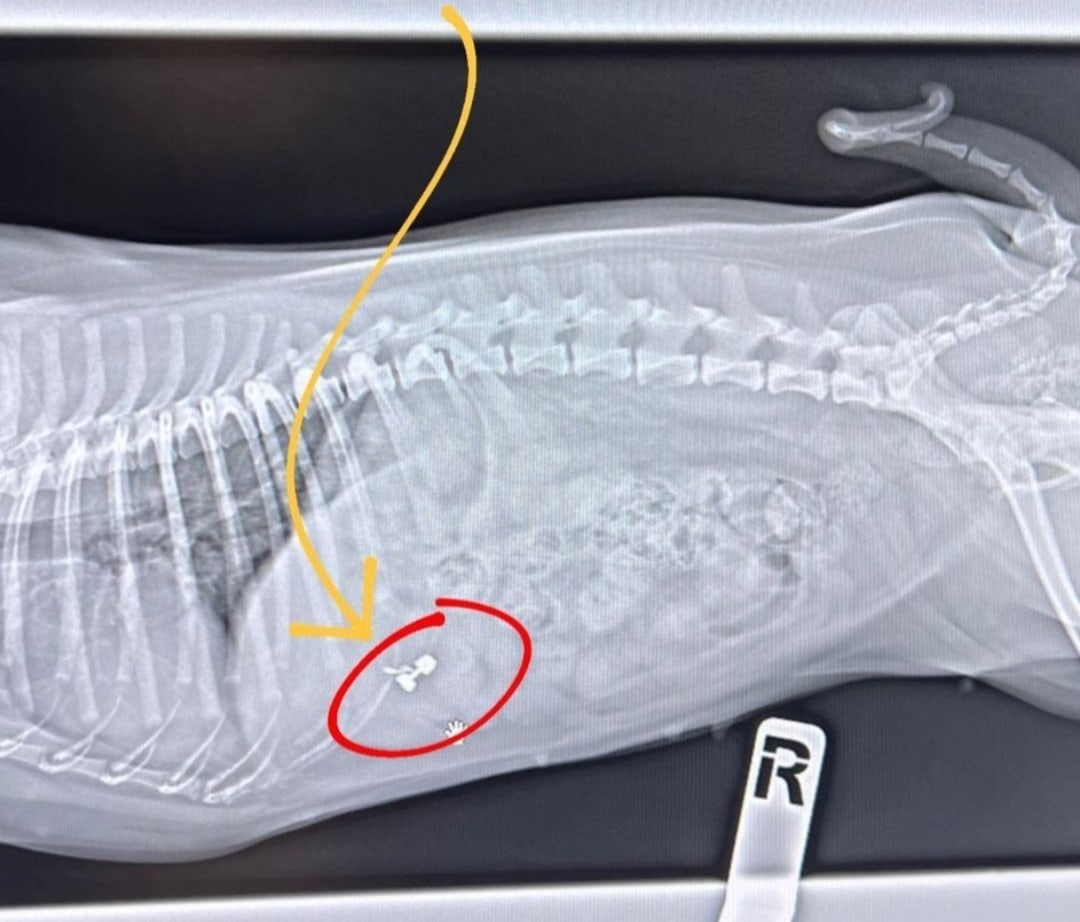

Пропажу получилось обнаружить внутри песика по результатам снимка, который пришлось сделать в ветеринарной клинике. Теперь знаменитой парочке придется долго ждать, когда дорогое украшение покинет организм собачки естественным путем. Фолловеры пожелали им терпения и в следующий раз лучше следить за мелкими деталями, ведь у них подрастает малыш.